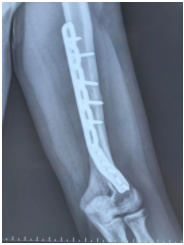

患者在韩国接受手术后复查的放射片

据悉,这名学生在韩国留学期间不慎发生意外,导致骨折,随后在当地医院接受了内固定手术。术后,学生发现手腕的功能并未得到恢复。经过一段时间的保守治疗,问题依旧没有改善,这让他感到极度焦虑和无助。由于语言和文化差异,以及家人无法照顾,他决定回到祖国,寻求国内专业医院的帮助。